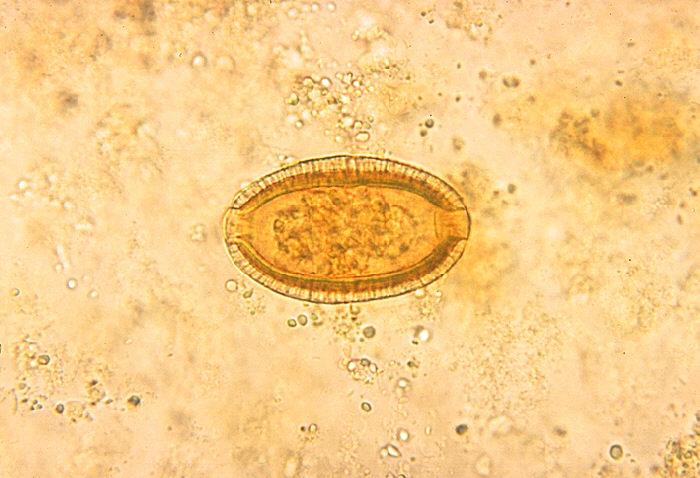

Капилляриоз у человека что это - фото презентация